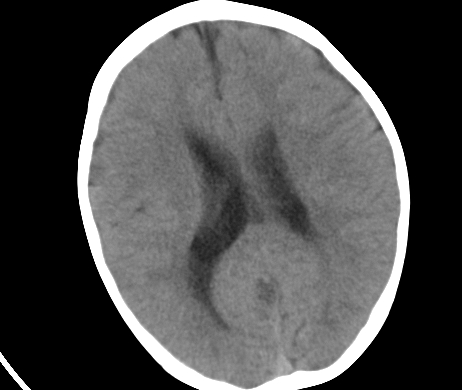

标题: PED1850:男 2岁 头部外伤1天,有事吗?

男 2岁 头部外伤1天,有事吗?科里意见不一 骨窗 没事,未上传

未见明显异常,必要时做mri

未见与外伤有关病变;脑白质的比例较少,有发育异常吗?